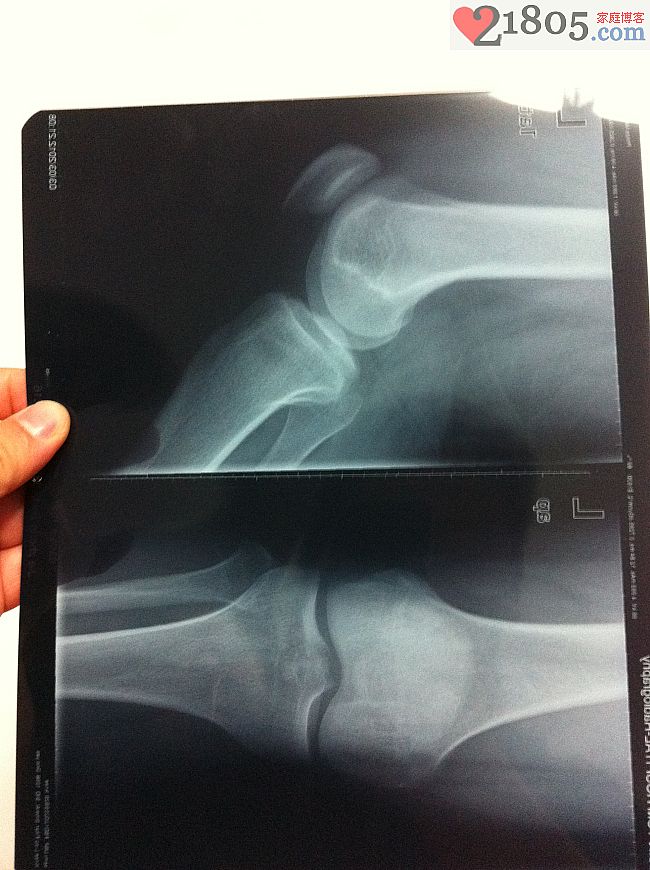

拍了片子,

显示膝盖周围没有明显骨折骨裂,

右膝盖周围X光片。